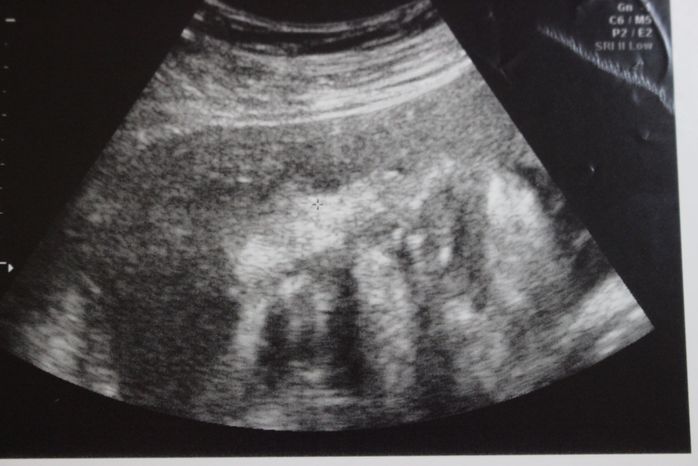

妊娠32週目のエコー写真

妊娠32週目。赤ちゃんの体重1915g。この頃の楽しみは医師軍団による回診で、ドラマ「白い巨塔」の再現VTRを見ているようでした。実家の母に頼んでウエストサイズ100cmのパジャマを作って送ってもらいました。